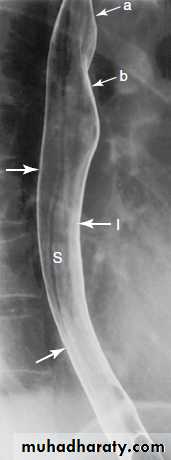

Films are taken with esophagus both full of barium to show the outline, and following the passage of the barium to show the mucosal pattern. The esophagus has a smooth outline when full of barium. When empty and contracted, barium normally lies in between the folds of mucosa, which appear as three or four long, straight parallel lines.

Aortic arch cause impression on the left side of the esophagus while the left main bronchus cause smaller impression below the esophagus. Peristaltic waves are observed during fluoroscopic control. Sometimes the contraction waves may not occur in an orderly fashion but are pronounced and prolonged giving the esophagus an undulated appearance (tertiary contractions)